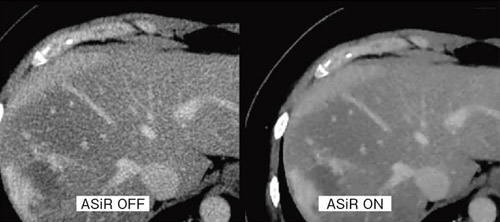

通常,ダイナミックスキャン時は,門脈と他の血管,実質とのコントラストがつきにくく,3D作成に時間を要することが多い。また,肝区域診断のため,静脈走行をアキシャル像で観察したい場合にもコントラスト差がなくなり,ウインドウを絞り込むと,ノイズが増加し読影が困難となることもある。ASiRでは,画像ノイズレベルを大きく低減するため,ルーチン的に行われているダイナミックスキャン時の門脈相,平衡相から再構成した静脈系アキシャル像の観察が容易になる(図3)。 |

図3 平衡相画像の比較 |